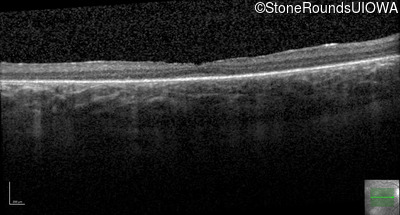

Optical Coherence Tomography - Right - 20/100

Exemplar / OCT Stack